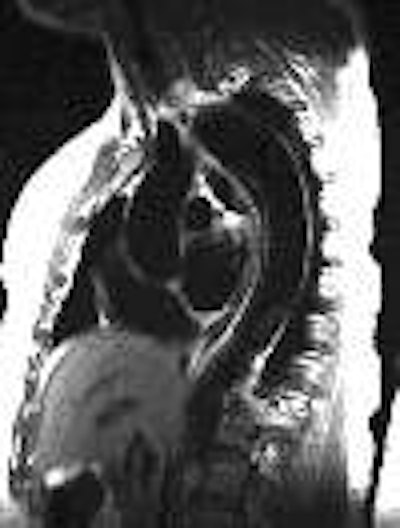

(1) Axial spin echo image showing the flap in the descending aorta: